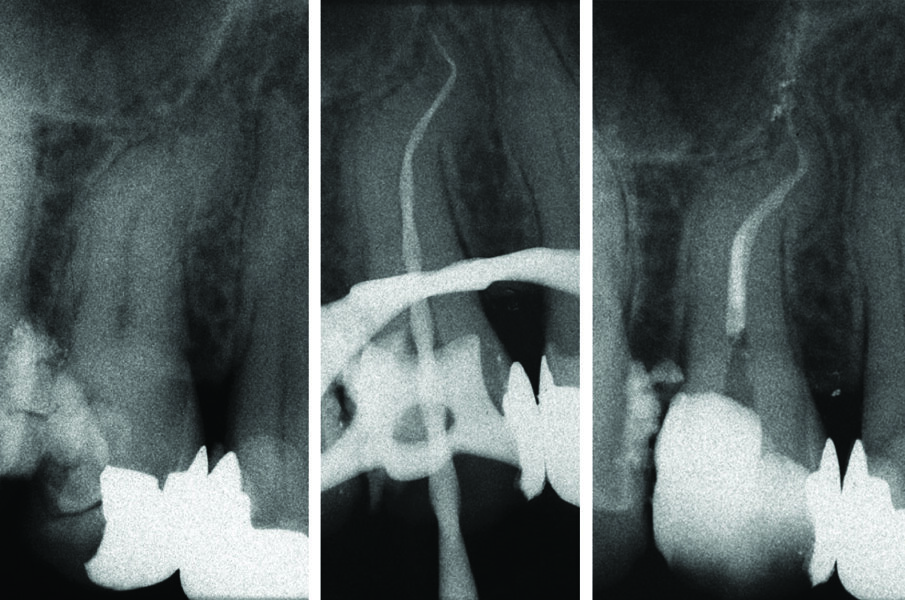

All’esame radiografico le otturazioni appaiono dense ed omogenee, la guttaperca mostra un buon adattamento alla morfologia endodontica, determinando un buon riempimento delle irregolarità del sistema canalare. Sono stati evidenziati la presenza di canali laterali ed uscite apicali multiple. Figg. 8a-8e molare superiore, Figg. 9a-9e molare inferiore, Figg. 10a-10c molare superiore, Figg. 11a-11d anatomie complesse premolare curvo e Figg. 12a-12d ottavo.

Fig. 1- Ritrattamento canalare 3.6 controllo a 5 anni.

Fig. 10 - Terapia canalare 1.5 doppia curva il canale preparato manualmente con Mtwo.